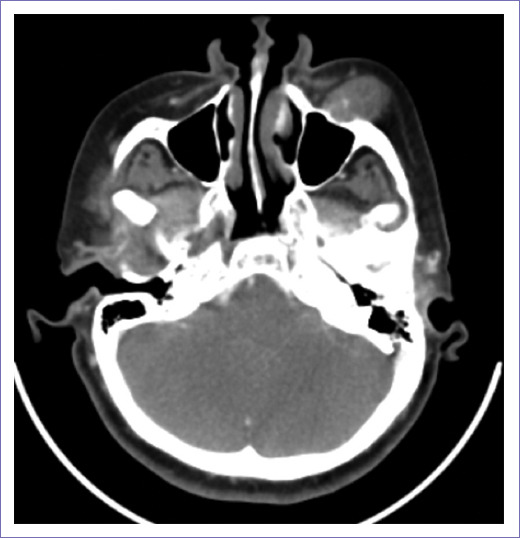

A face CT scan revealed a heterogeneous left maxillary tumor with bone destruction, which measured 34 × 28 mm, extending into surrounding soft tissue and masticator space, with an invasion of the hard and soft palate (Fig. 2). No adenopathy was identified. A left infrastructural maxillectomy was performed. The tumor was resected entirely, a solid tumor was identified, measuring approximately 4 × 4 cm, with intimate contact with the orbit floor, without infiltrating it. Furthermore, infiltration to the hard palate, up to the midline, was observed (Fig. 3 A, B, C). The post-operative period was uneventful, and she was discharged on post-operative day 4. Final histopathological examination reported a myoepithelial maxillary carcinoma. Immunohistochemical staining revealed positive for S100, calponin, and P63 negative. Adjuvant radiotherapy, with 60 Gy, was administered.